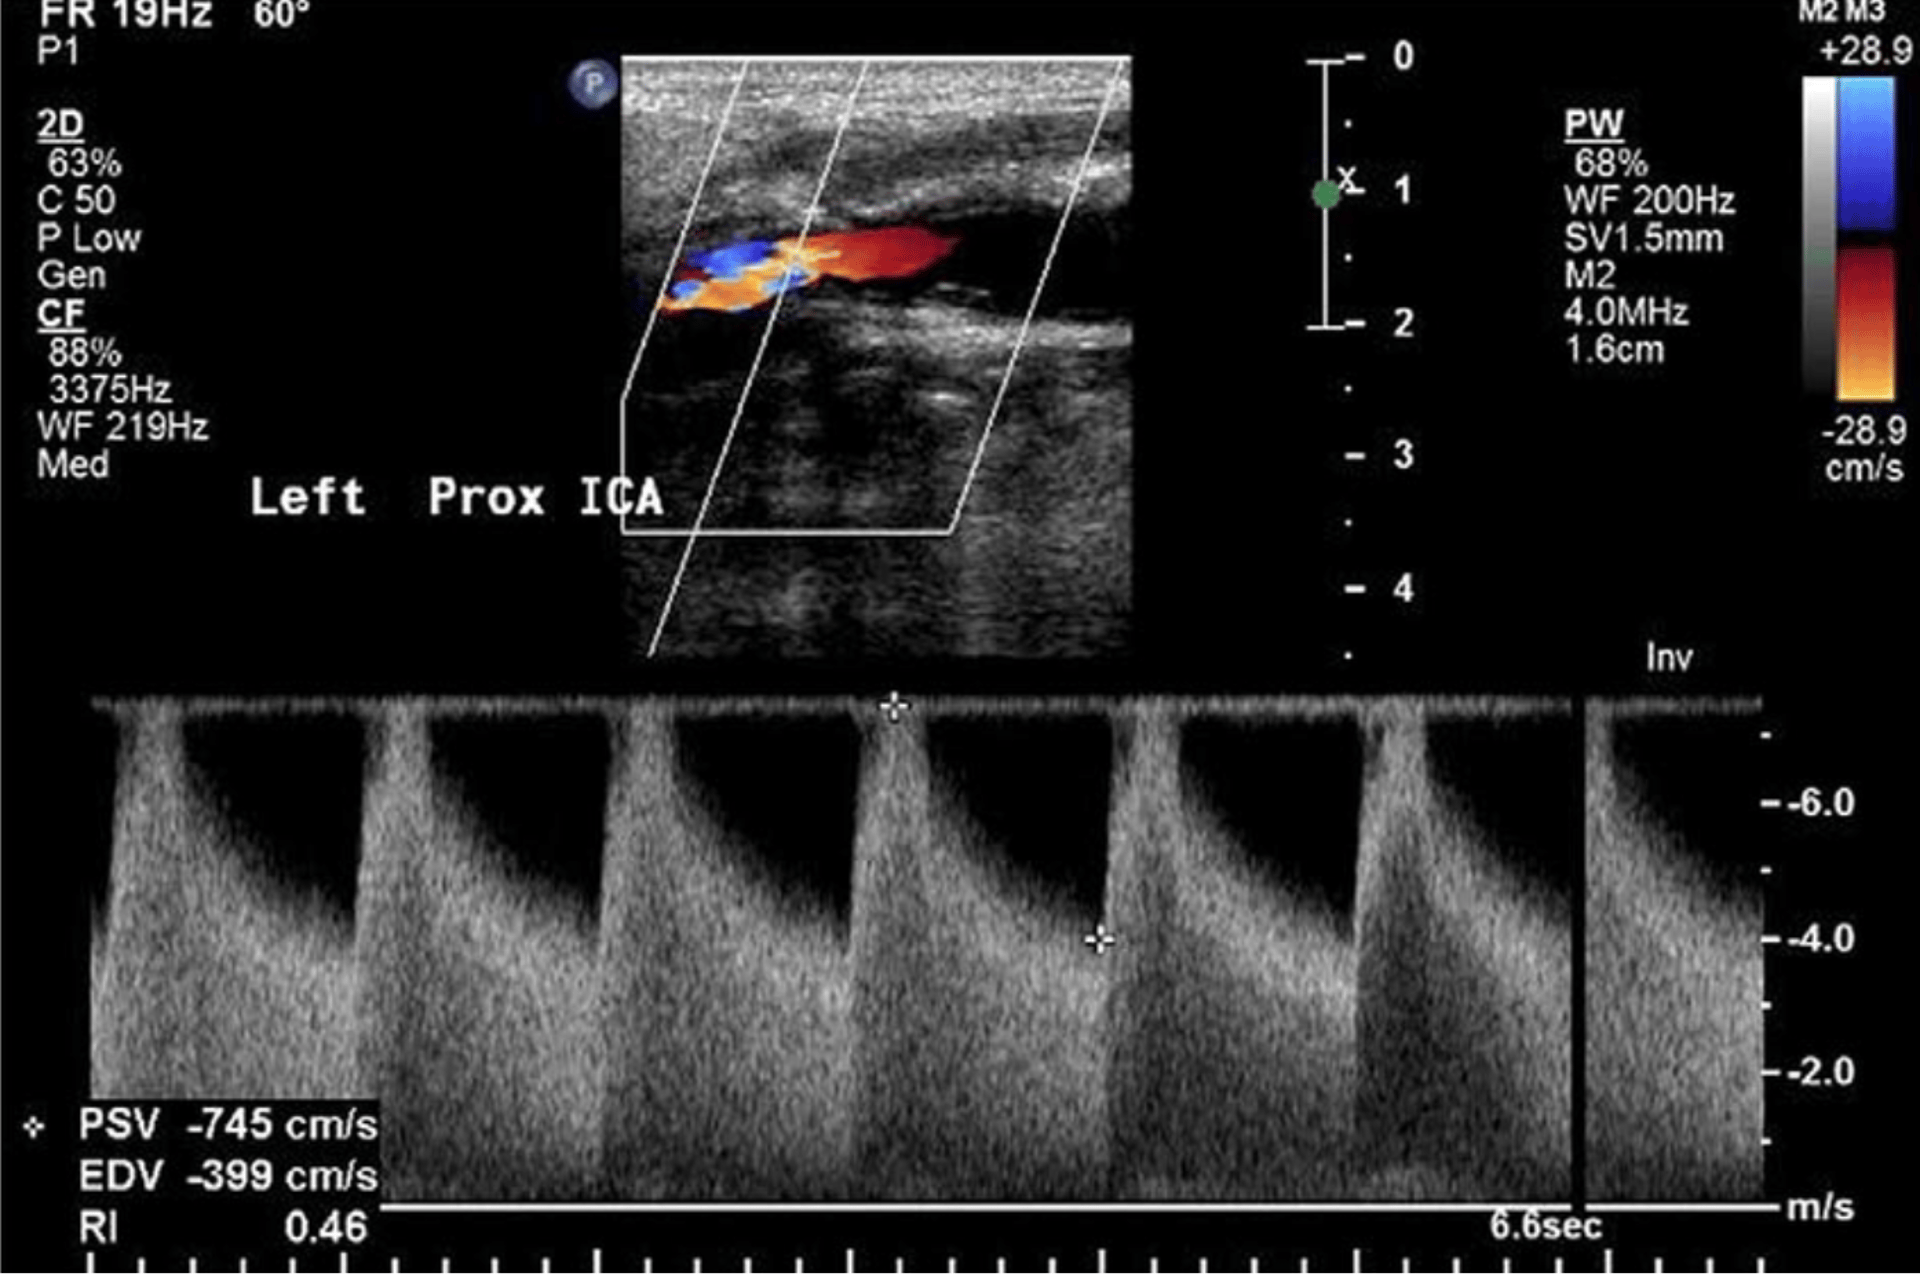

Carotid and vertebral artery evaluation.

Physiologic correlation with symptoms: flow, waveform patterns, and change over time.

Risk-stratified follow-up for known stenosis or post-intervention monitoring.

Hemodynamics matter. Doppler adds a physiologic layer that complements imaging — trends, flow direction, resistance patterns, and response to change.